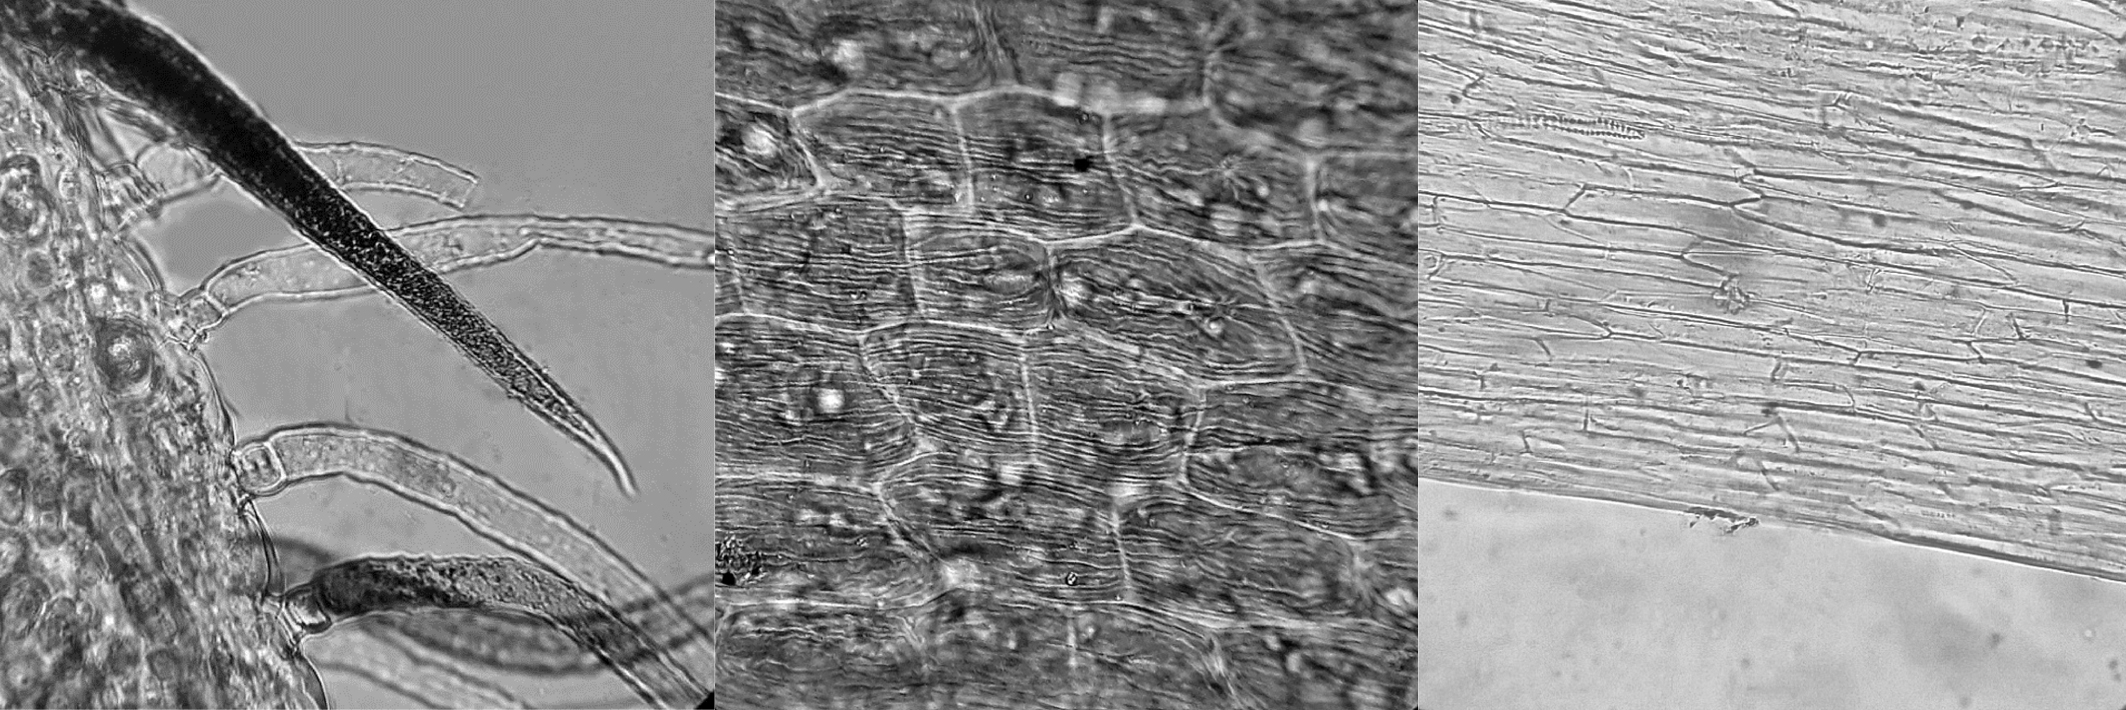

При рассмотрении листа с поверхности видны клетки верхнего эпидермиса со слабоизвилистыми стенками, иногда прямостенные с четко видным утолщением клеточных стенок. Клетки нижнего эпидермиса извилистостенные со слегка заметной продольной морщинистостью кутикулы. Устьица расположены в основном на нижнем эпидермисе, окружены 3–4 клетками, не отличающимися от основных клеток эпидермиса (аномоцитный тип). Вдоль жилки клетки эпидермиса прозенхимной формы с прямыми или со скошенными конечными клетками. Волоски простые, двуклеточные, толстостенные, с очень короткой базальной клеткой и длинной конечной (терминальной) клеткой с бугорчатой поверхностью, равномерно располагаются по поверхности листа. Вокруг волосков клетки эпидермиса расположены лучисто, образуя розетку. Часто в сырье по эпидермису листа можно встретить такие розетки из клеток эпидермиса на месте прикрепления волоска (рисунок 2).

Рисунок 2. Микродиагностические признаки листа астрагала солодколистного. 1 – фрагмент верхнего эпидермиса листа с розеткой из клеток эпидермиса на месте прикрепления волоска и клетками эпидермиса со слабоизвилистыми стенками (200х), 2 – фрагмент верхнего эпидермиса листа с простым двуклеточным волоском (100х), 3 – фрагмент эпидермиса вдоль жилки листа с клетками прозенхимной формы (200х), 4 – розетка эпидермиса на месте прикрепления волоска (100х), 5 – фрагмент края листа с простыми двуклеточными волосками (100х), 6 – фрагмент нижнего эпидермиса листа с устьицами и извилистостенными клетками эпидермиса (100х).